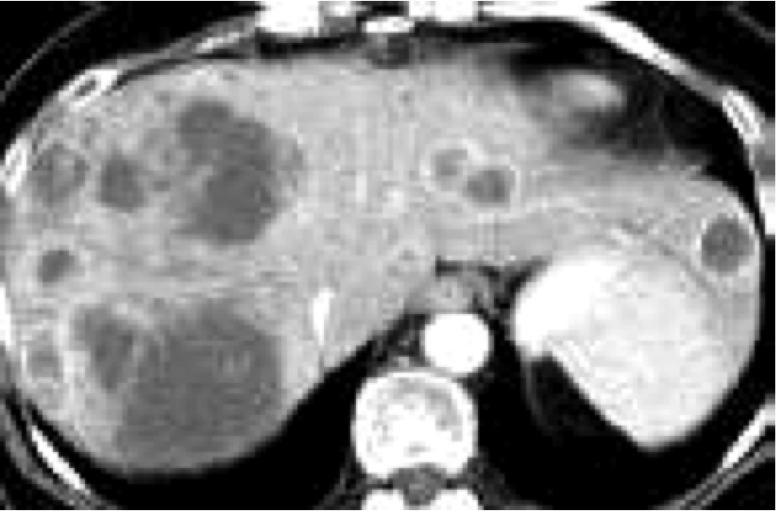

MC metastatic site = liver (CT scan)